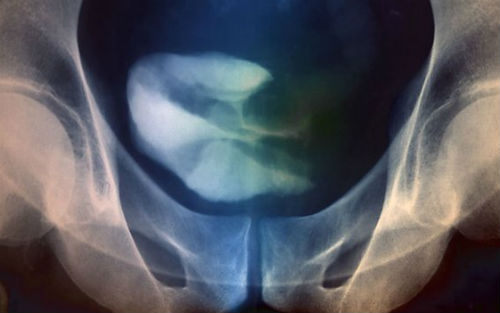

近日,发表在《自然》杂志上的一项研究中,伦敦玛丽皇后大学的科学家们实现了治疗晚期膀胱癌的重大突破。在过去的三十年里,晚期膀胱癌的治疗没有任何的重大进展。研究检测了阻断PD-L1的抗体MPDL3280A的治疗效果,PD-L1是一种帮助癌细胞躲避免疫系统检测的蛋白。

膀胱癌是英国排名第七的癌症,约10%的患者在诊断时已经是晚期了。这让治疗变得非常困难,化疗是唯一的选择。很多人最终因为化疗的毒性大、作用小而放弃了治疗;患者在确诊后的平均生存期为12-18个月。

第一阶段的国际多中心临床试验中,68名晚期膀胱癌患者(其它标准治疗已经对这些患者无效了,如化疗)接受了罗氏研发的癌症免疫治疗药物MPDL3280A。这些患者还接受了蛋白PD-L1的检测,其中大约30名患者被确定为PD-L1阳性肿瘤。

治疗6周后,43%的PD-L1阳性患者的肿瘤缩小了;12周后,比例上升到52%。在随后的治疗中,这些患者中有2人(7%)放射成像检测发现不再有癌症迹象。在PD-L1阴性患者中,也有11%的患者对治疗有积极的响应。